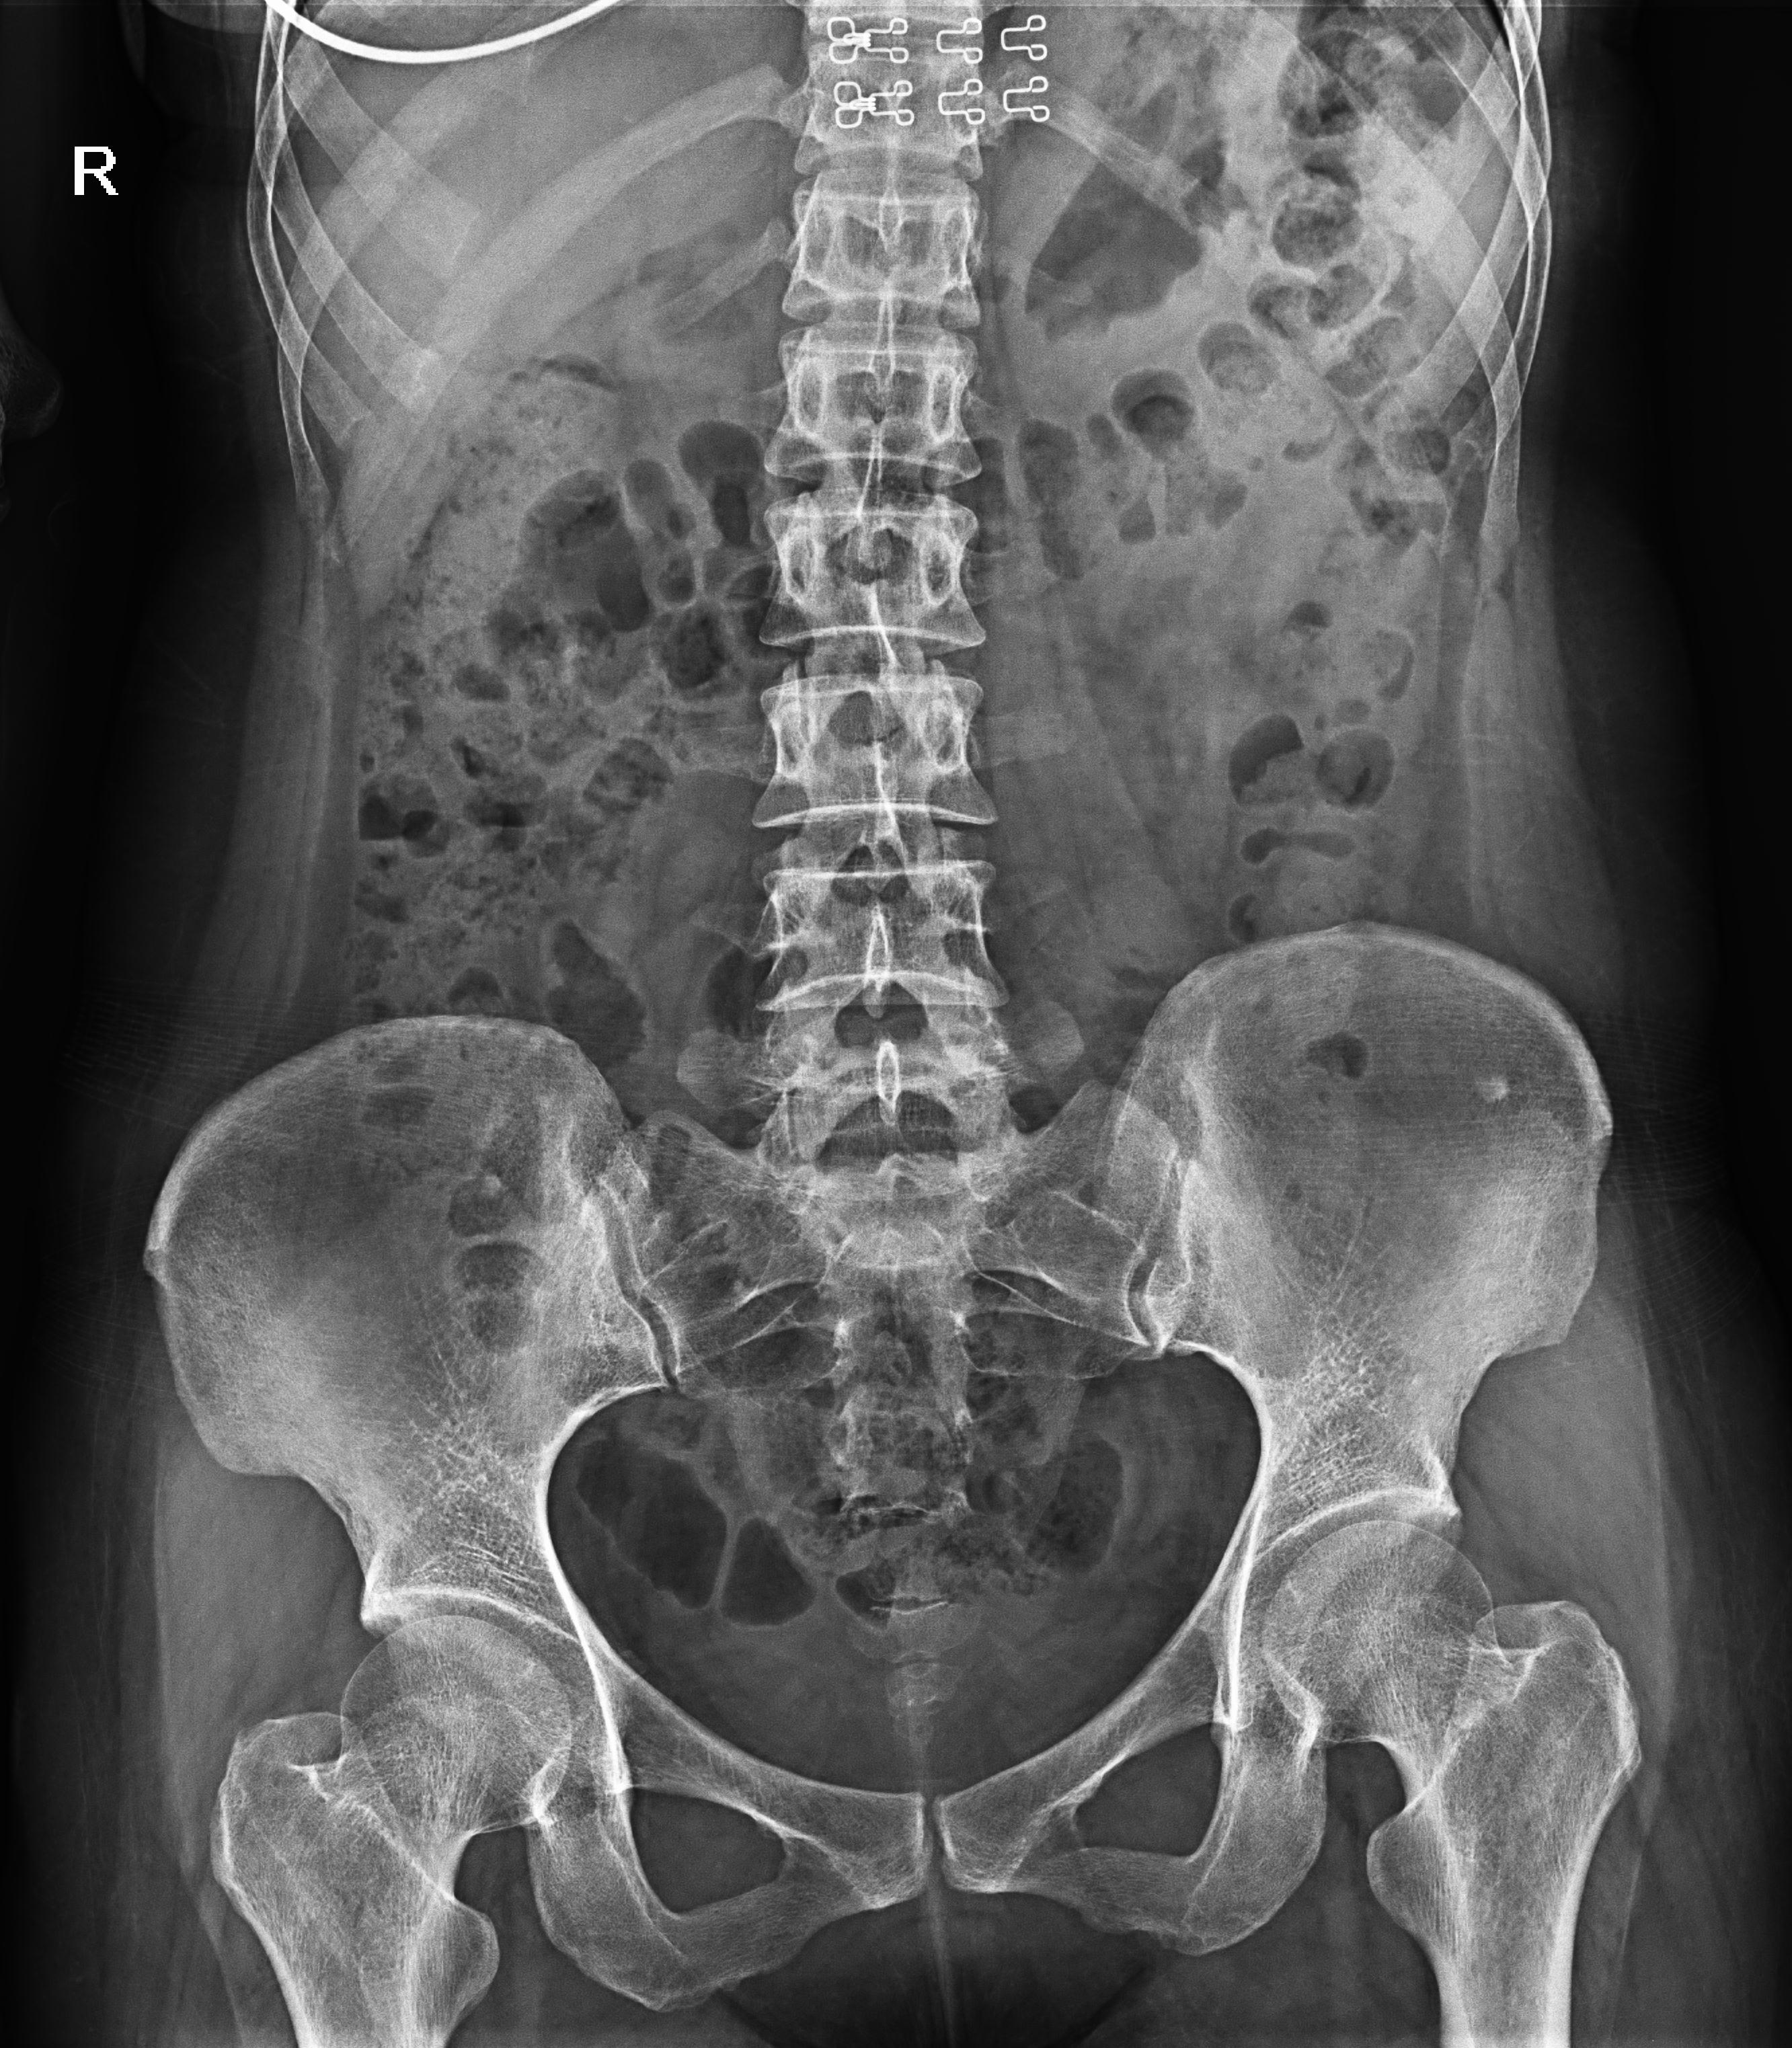

拉伸自如:SID電動拉伸,最長可延伸至1.8米,滿足放射科室各種拍片距離的需求。如:GBZ 70-2015職業性塵肺病的診斷標準中對胸片拍片距離1.8米的要求。

點片裝置移動范圍大,無需患者移動就能完成全身各部位的檢查;

床面橫向移動,輕松實現機動人不動。